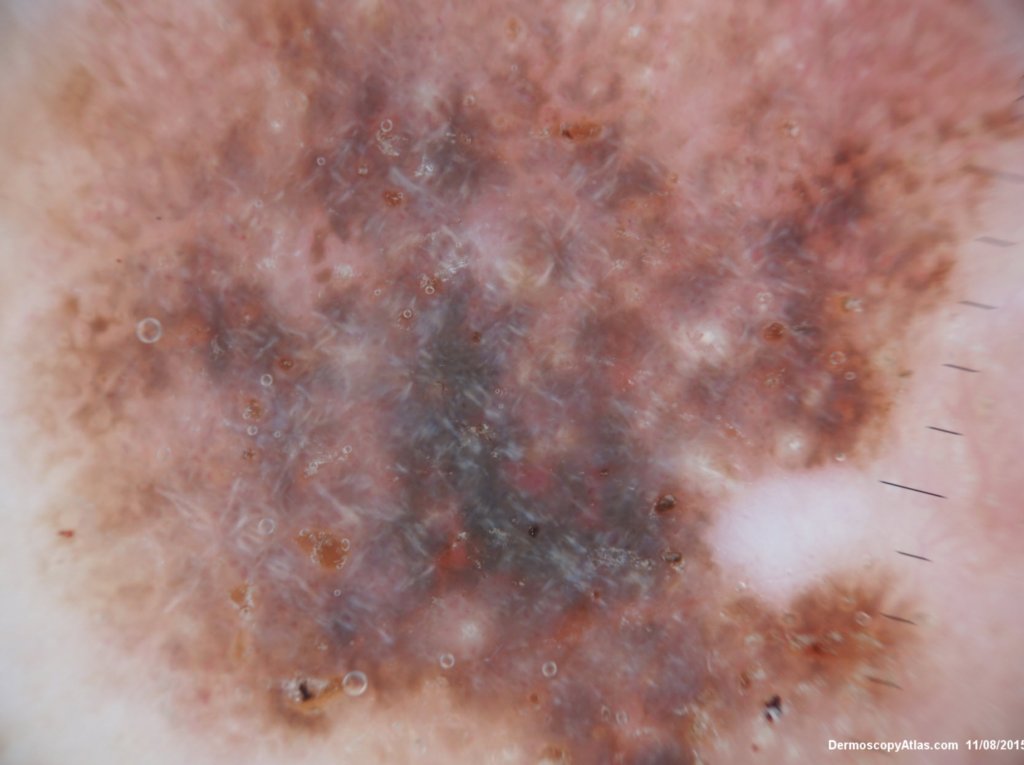

Site: Back

Diagnosis: Seborrhoeic keratosis irritated

Sex: M

Age: 92

Description: Pigmented lesion back

This lesion looked darker than the many other seborrhoeic keratoses on this elderly man's back. It was thought there might be a lentiginous proliferation of atypical melanocytes in the lesion . Also the multiple colours and the white lines were unusual for a seborrhoeic keratosis. However pathology of a large shave biopsy excision showed only a pigmented thick seborrhoeic keratosis with increased pigment in normal basal keratinocytes. The blue colour was because of the depth of the lesion ie thick. No idea why the white lines!